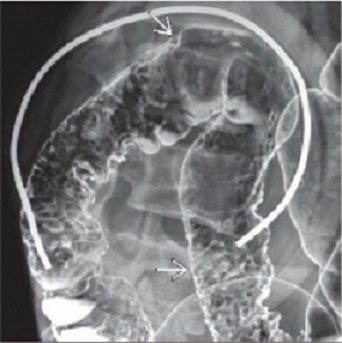

Aspect radiologique de lavement baryte

mono de contrast et

a double de contrast est : Image en lacule a bord

lisse a sessile ou pedicule . Technique a double de

contrast peut se donne des images de polyp en face anterieure

et posterieure du colon .

Aspect laculaire a bord

lisse pedicule d'une polyp du colon ascendant (

fleche rouge ) . Image radiologique de lavement

baryte a mono- contrast du colon . |